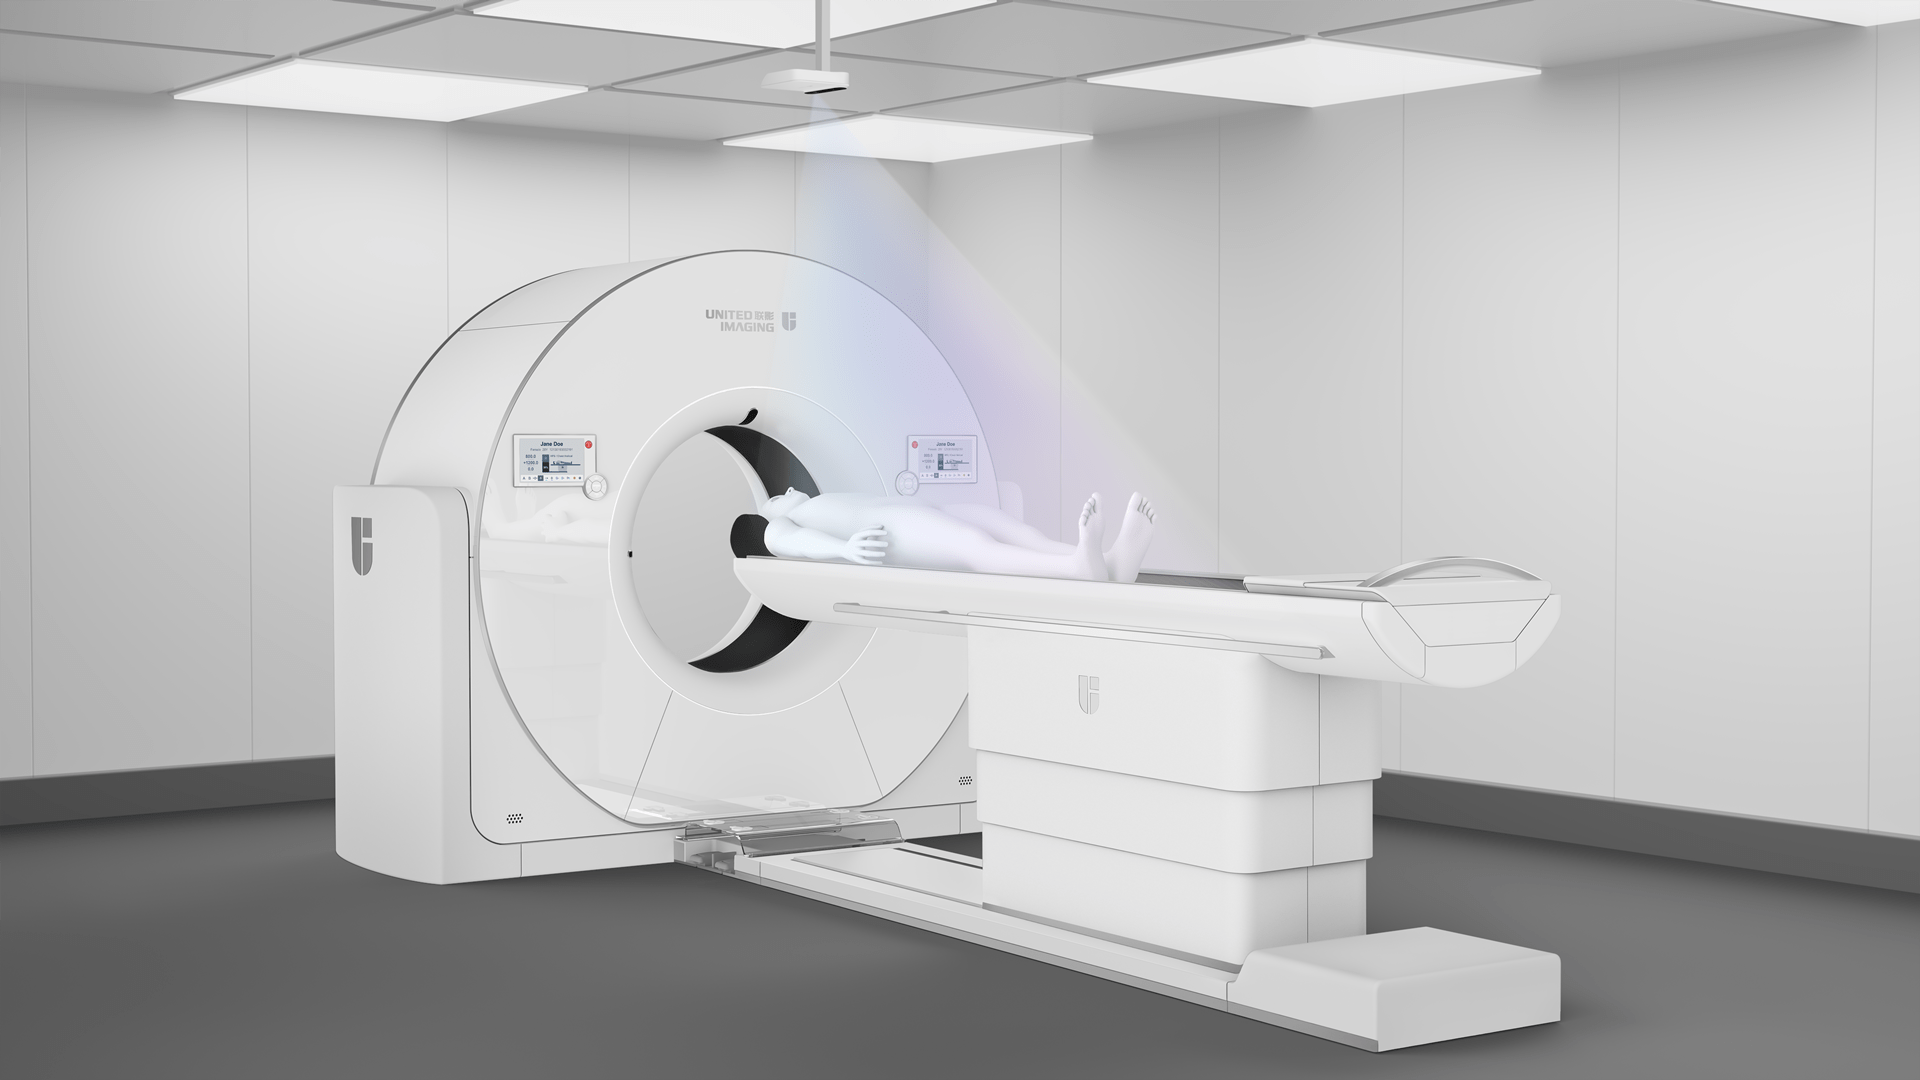

全能升维 解锁想象

作为超高端640层CT,天河640突破技术边界,搭载领先业界的人工智能技术,“冻结”人体生理运动,优化CT扫描与操作流程;提供单心动周期内的自由心脏成像、肿瘤功能成像、4D一站式卒中成像等多场景解决方案, 为临床和科研开启无限想象空间。

大孔径带来舒适检查体验;亚秒完成全肺成像,受检者无需屏气

3D打印精密工艺三维防散射栅格、Real 3D Full大锥角重建算法等多重硬件、软件技术协同,克服宽体探测器的核心技术挑战,天河640单圈扫描即可获得高质量的全脑、全冠脉轴扫图像